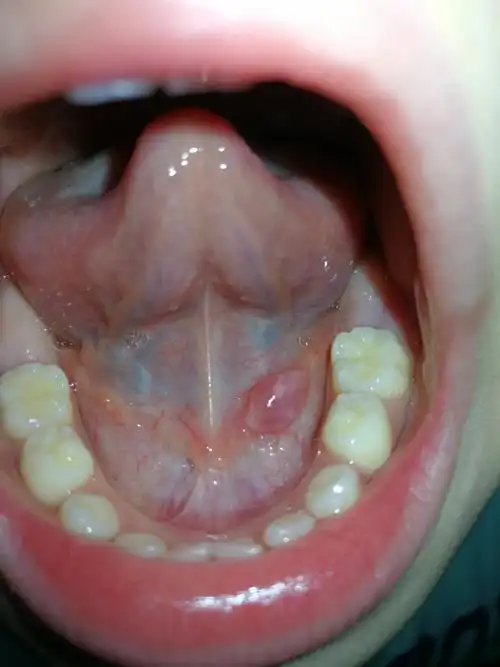

儿子舌头底下有个小肉芽,早就有,但是最近几天长大了,长的挺快